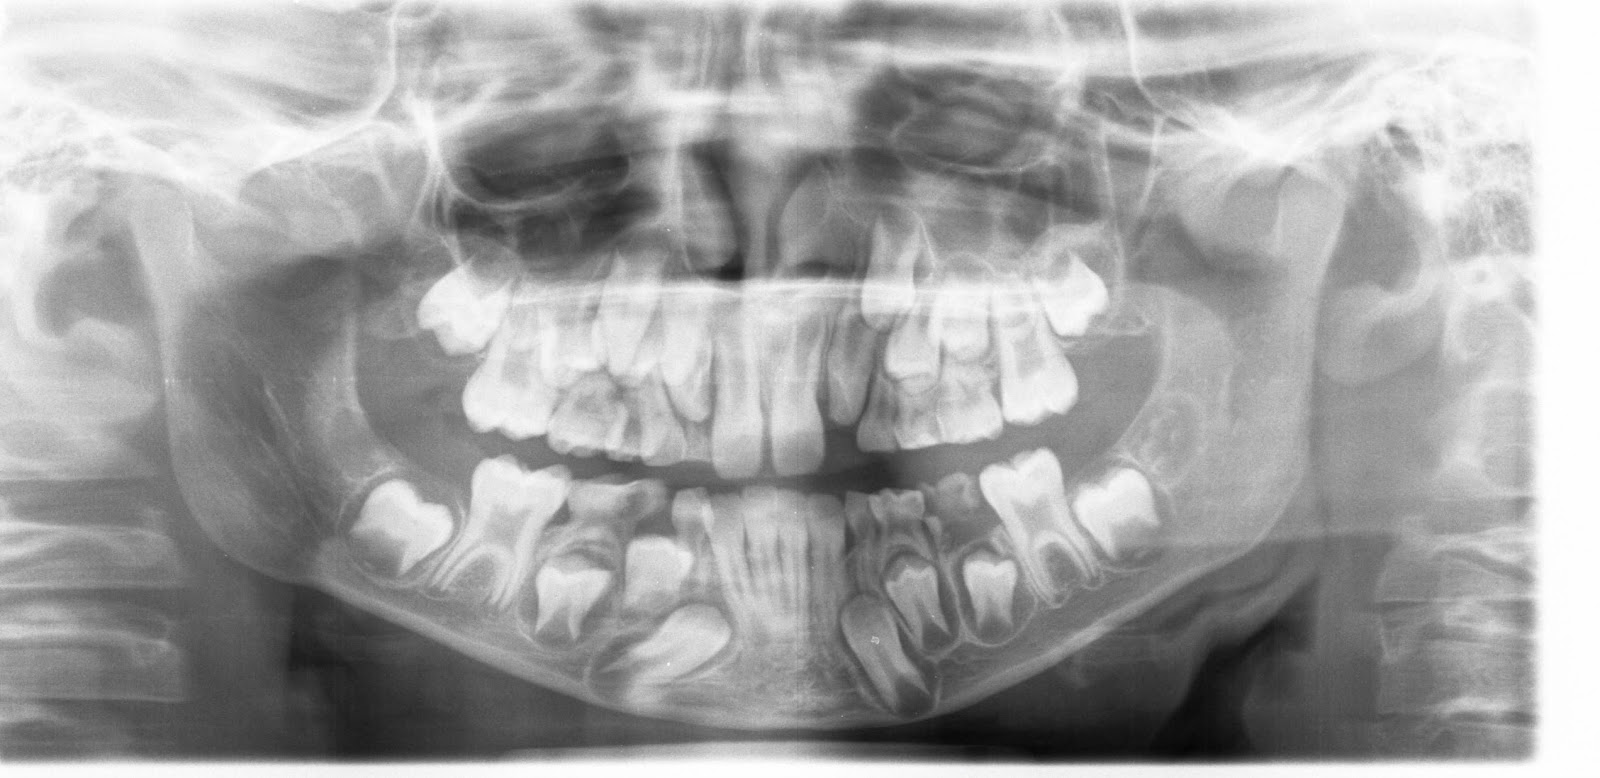

Ao Leo caiulle o outro día un dente e aínda lle faltan algúns por caíren. Na foto mírase a irrupción dos dentes novos que uns van ben polo sitio dos de leite e outros entran de lado ou de langueta.

Txiiiiiiiiiiiiiiiii. A julgar pelo RX pode ir preparando a verba para um aparelho corrector.